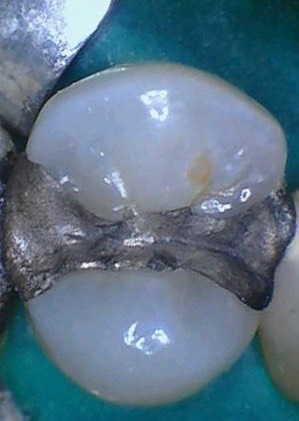

Mendel Sato #12 pre-op